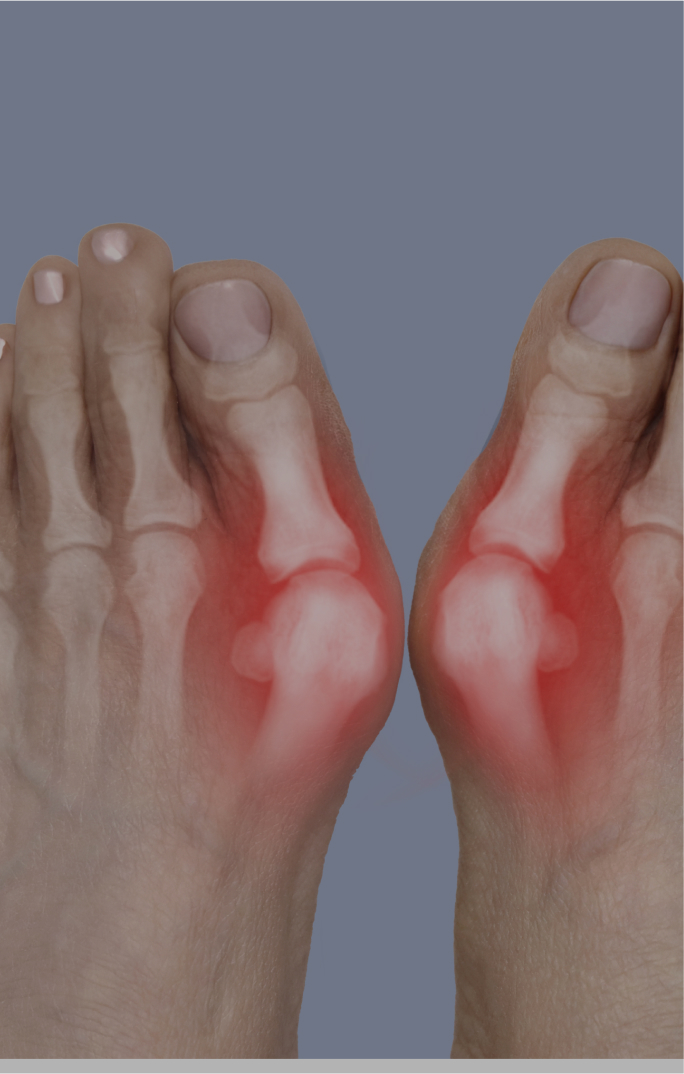

기능 문제뿐 이니라 미용적 스트레스까지

유발하던 무지 외반증.

• 01.통증/염증으로 보행이 불편한 경우

• 02.변형 각도 20도 이상 (3~4단계)

• 03.깔창·신발로 호전되지 않는 진행성 무지외반증

• 04.미용적으로 개선을 원하는 경우